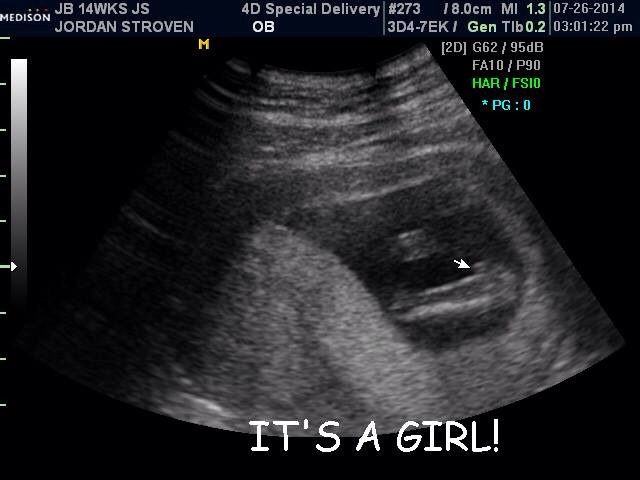

Hi ladies! I just found this site today and I'm so excited and wish I would have found it sooner!! I have a few pictures I'm going to try and upload, one is from my Dr at 12w5d just to show the skull and nub theory, I'm not great about that but just maybe to help. Lol the next is at 13w5d from an elective scan I had to try and see the gender. They leaned towards girl but I'll confirm with my actual Dr sep 5th, it's killing me waiting though! I've had mixed reviews from everyone I've shown! Some say girl, some say boy, some say to keep receipts of I buy pink.... It's so confusing! I wouldn't be so doubtful I think had so many people question the scan, and the fact it took forever to even get a hint! Baby was stubborn! It was supposed to take 15 minutes, took 45.... Two techs.... Me having to get up and move around multiple times. Lol it was a show!

I'm thinking this probably should have been done on my laptop now. I can't organize them very well on my phone, the side view on 2d was at 12w5d everything else like the 3d and between the leg shots were all taken 13w5d I hope that makes sense!